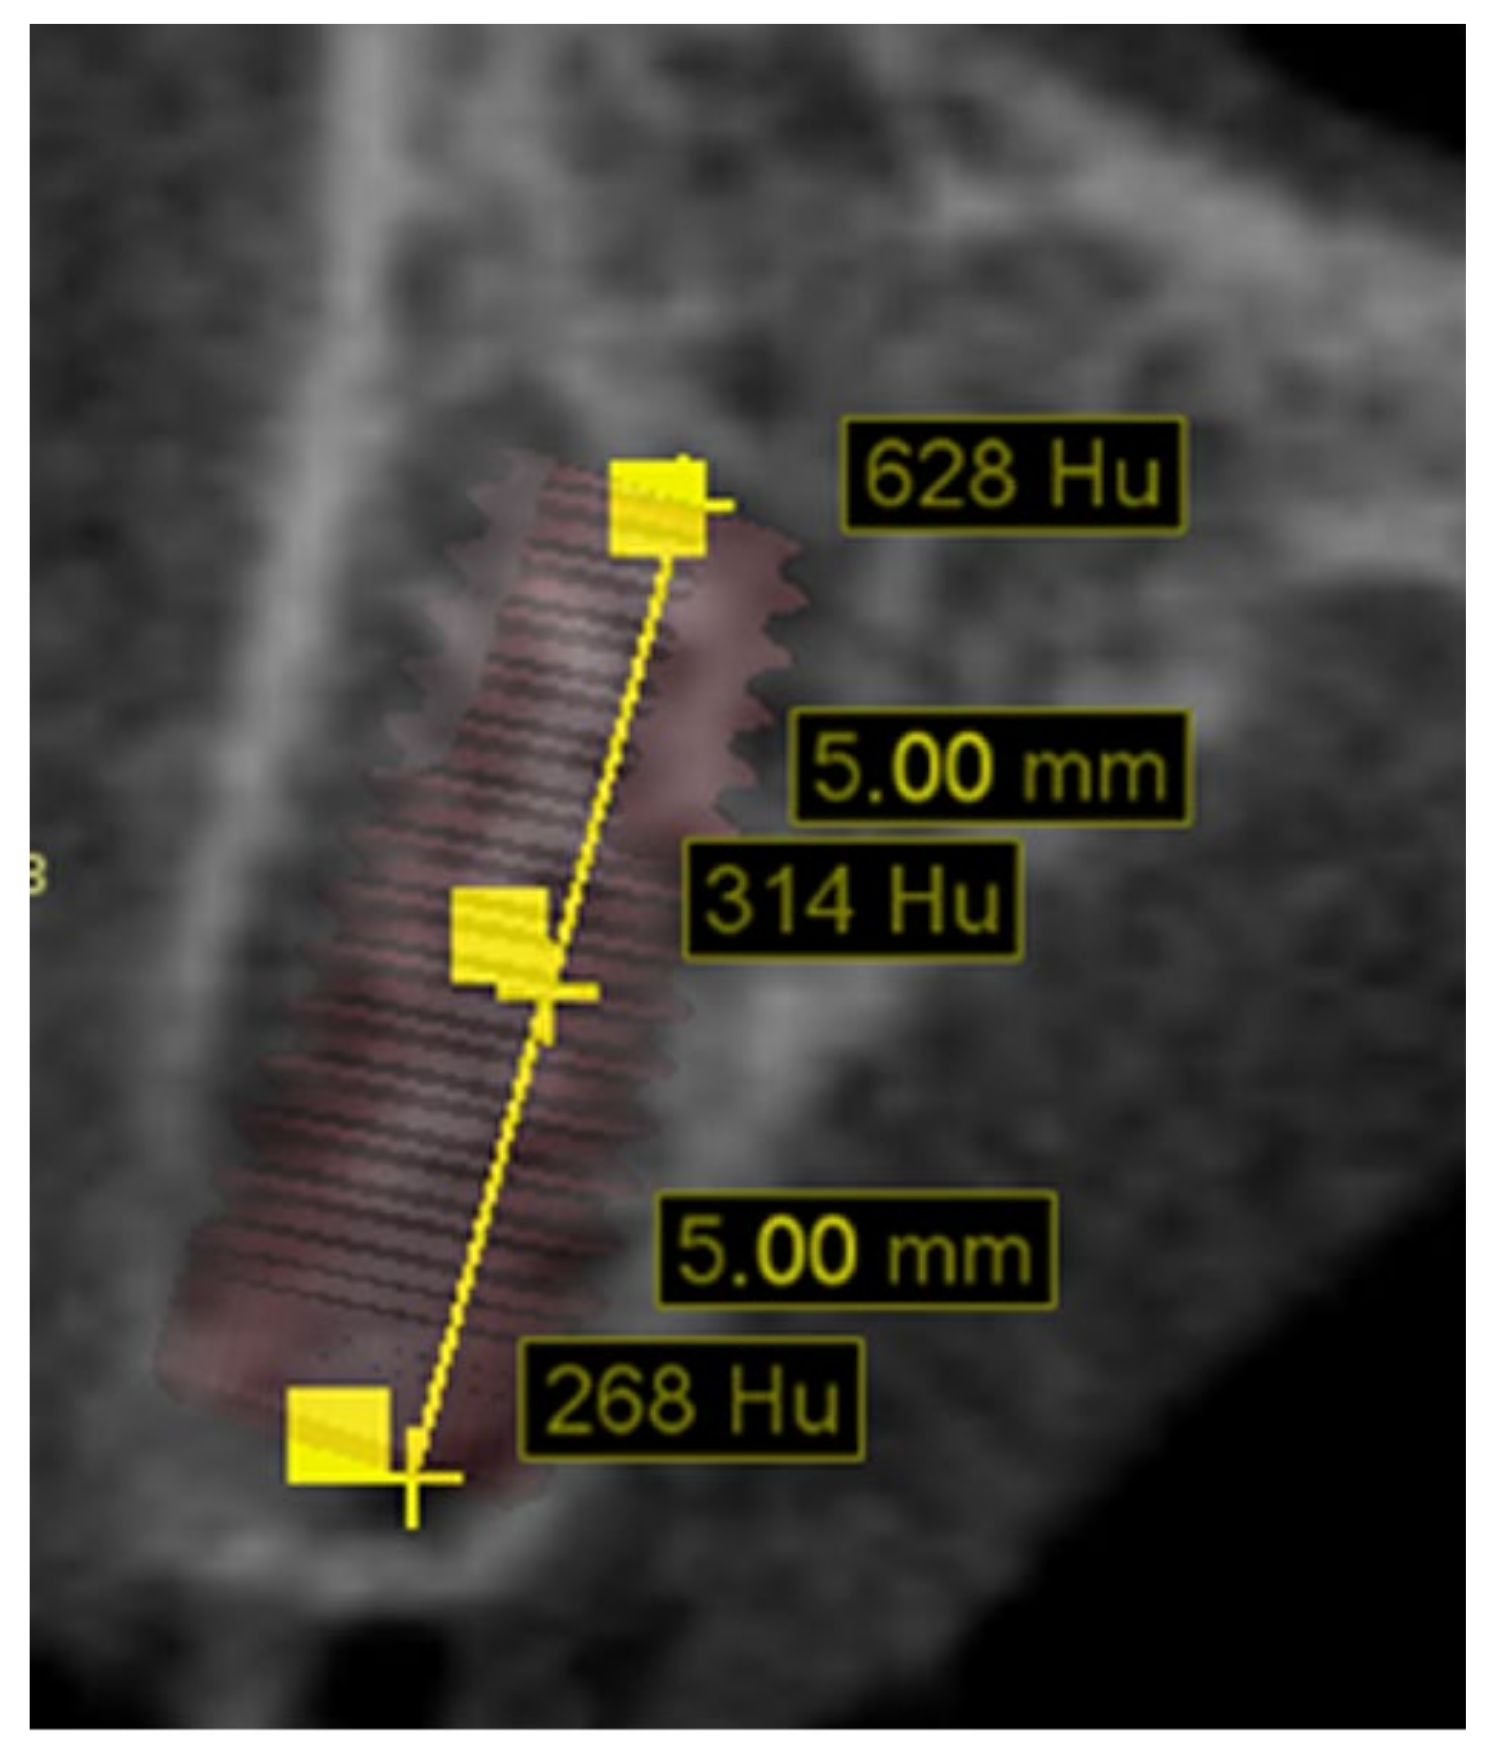

| Group | Patients | Implants Areas | Bone Density | |||

|---|---|---|---|---|---|---|

| Cervical | Body | Apical | Mean | |||

| Osseodensification + healing chamber | 14 | 29 | 529 ± 226 | 389 ± 255 | 433 ± 207 | 450 ± 171 |

| Standard undersized | 16 | 26 | 483 ± 181 | 410 ± 213 | 481 ± 198 | 458 ± 115 |

| p-value | 0.420 | 0.744 | 0.398 | 0.852 | ||